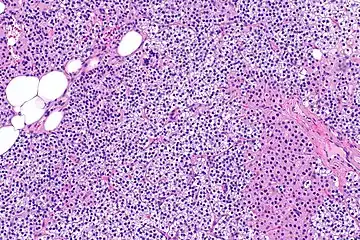

Parathyroid hyperplasia low mag.

Primary hyperplasia of the parathyroid gland, results from both hypocalcaemia and increased phosphate levels by decreasing expression of calcium sensing receptors and vitamin D receptors at the parathyroid gland.[8][4] These decreases in receptor expression lead to hyperfunctioning of the parathyroid. Hyperfunction of the parathyroid gland is thought to exacerbate primary hyperplasia which evolves further to a secondary more aggressive hyperplasia. Histologically, these hyperplasic glands can be either diffuse or nodular.[24] Primary hyperplasia, usually resulting in diffuse polyclonal growth is manly related to reversible secondary hyperparathyroidism. Secondary hyperplasia of the parathyroid gland is more often a nodular, monoclonal growth that sustains secondary hyperparathyroidism and is the catalyst in the progression to tertiary hyperparathyroidism. Nodular hyperplastic glands in tertiary hyperparathyroidism are distinctly larger in both absolute size and weight up to 20-40-fold increases have been reported.[25][26][24]

Parathyroid glands are normally composed of chief cells, adipocytes and scattered oxyphil cells.[27][14] Chief cells are thought to be responsible for the production, storage and secretion of parathyroid hormone. These cells appear light and dark with a prominent Golgi body and endoplasmic reticulum. In electron micrographs, secretory vesicles can be seen in and around the Golgi and at the cell membrane. These cells also contain prominent cytoplasmic adipose.[27][14] Upon onset of hyperplasia these cells are described as having a nodular pattern with enlargement of protein synthesis machinery such as the endoplasmic reticulum and Golgi. Increased secretory vesicles are seen and decreased intercellular fat is characteristic.[27][24] Oxyphil cells also appear hyperplasic however, these cells are much less prominent.